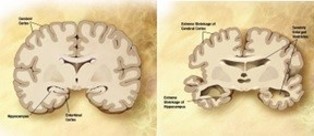

Symptoms of AD affecting the CNS

Alzheimer’s starts in the central nervous system and pro- gresses slowly from there. AD is characterized by decreasing ar- eas of the brain, damage to tissue cells, and the breakdown of neuronal connection links [18]. Tangles and amyloid plaques ac- cumulated in the brain are also thought to be a characteristic of AD. Studies of brain metabolism using MRI and PET, along with other imaging modalities, have revealed distinctive alterations in AD patients [3]. Figure 1 displays an MRI of a brain affected by AD and a normal brain [1]. Artificial intelligence has a significant role in the diagnosis of AD.

In AD affected brain the ventricles in center of the region enlarges and the cortical gray area in the corners of the brain reduces [9].

Non-demented very mild mild moderate